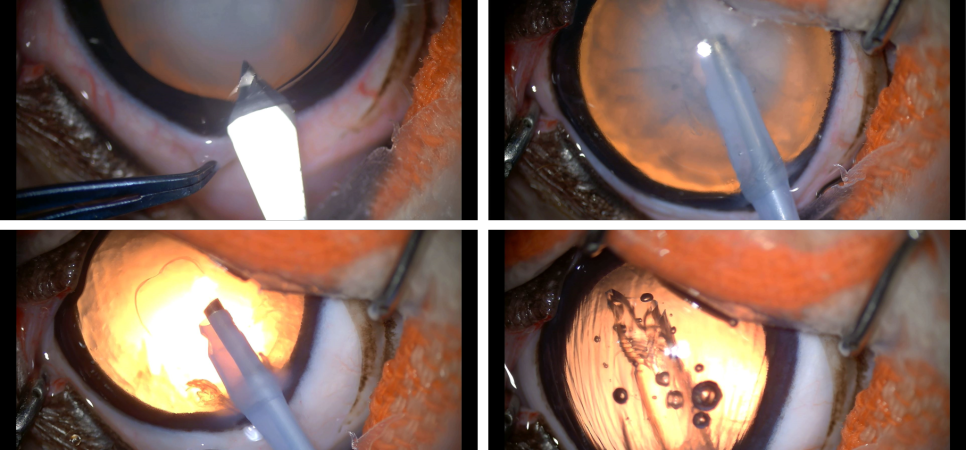

사진과 같이 각막을 절개하여 눈 속에 기구를 삽입하여 수정체 내의 딱딱해진 백내장을 초음파로 녹여 흡인, 제거합니다.백내장 물질이 눈에서 사라졌기 때문에 정상적인 오렌지색 반사가 밝아 보이는 것을 확인한 후 인공렌즈를 눈 속에 서서히 펴서 삽입합니다.